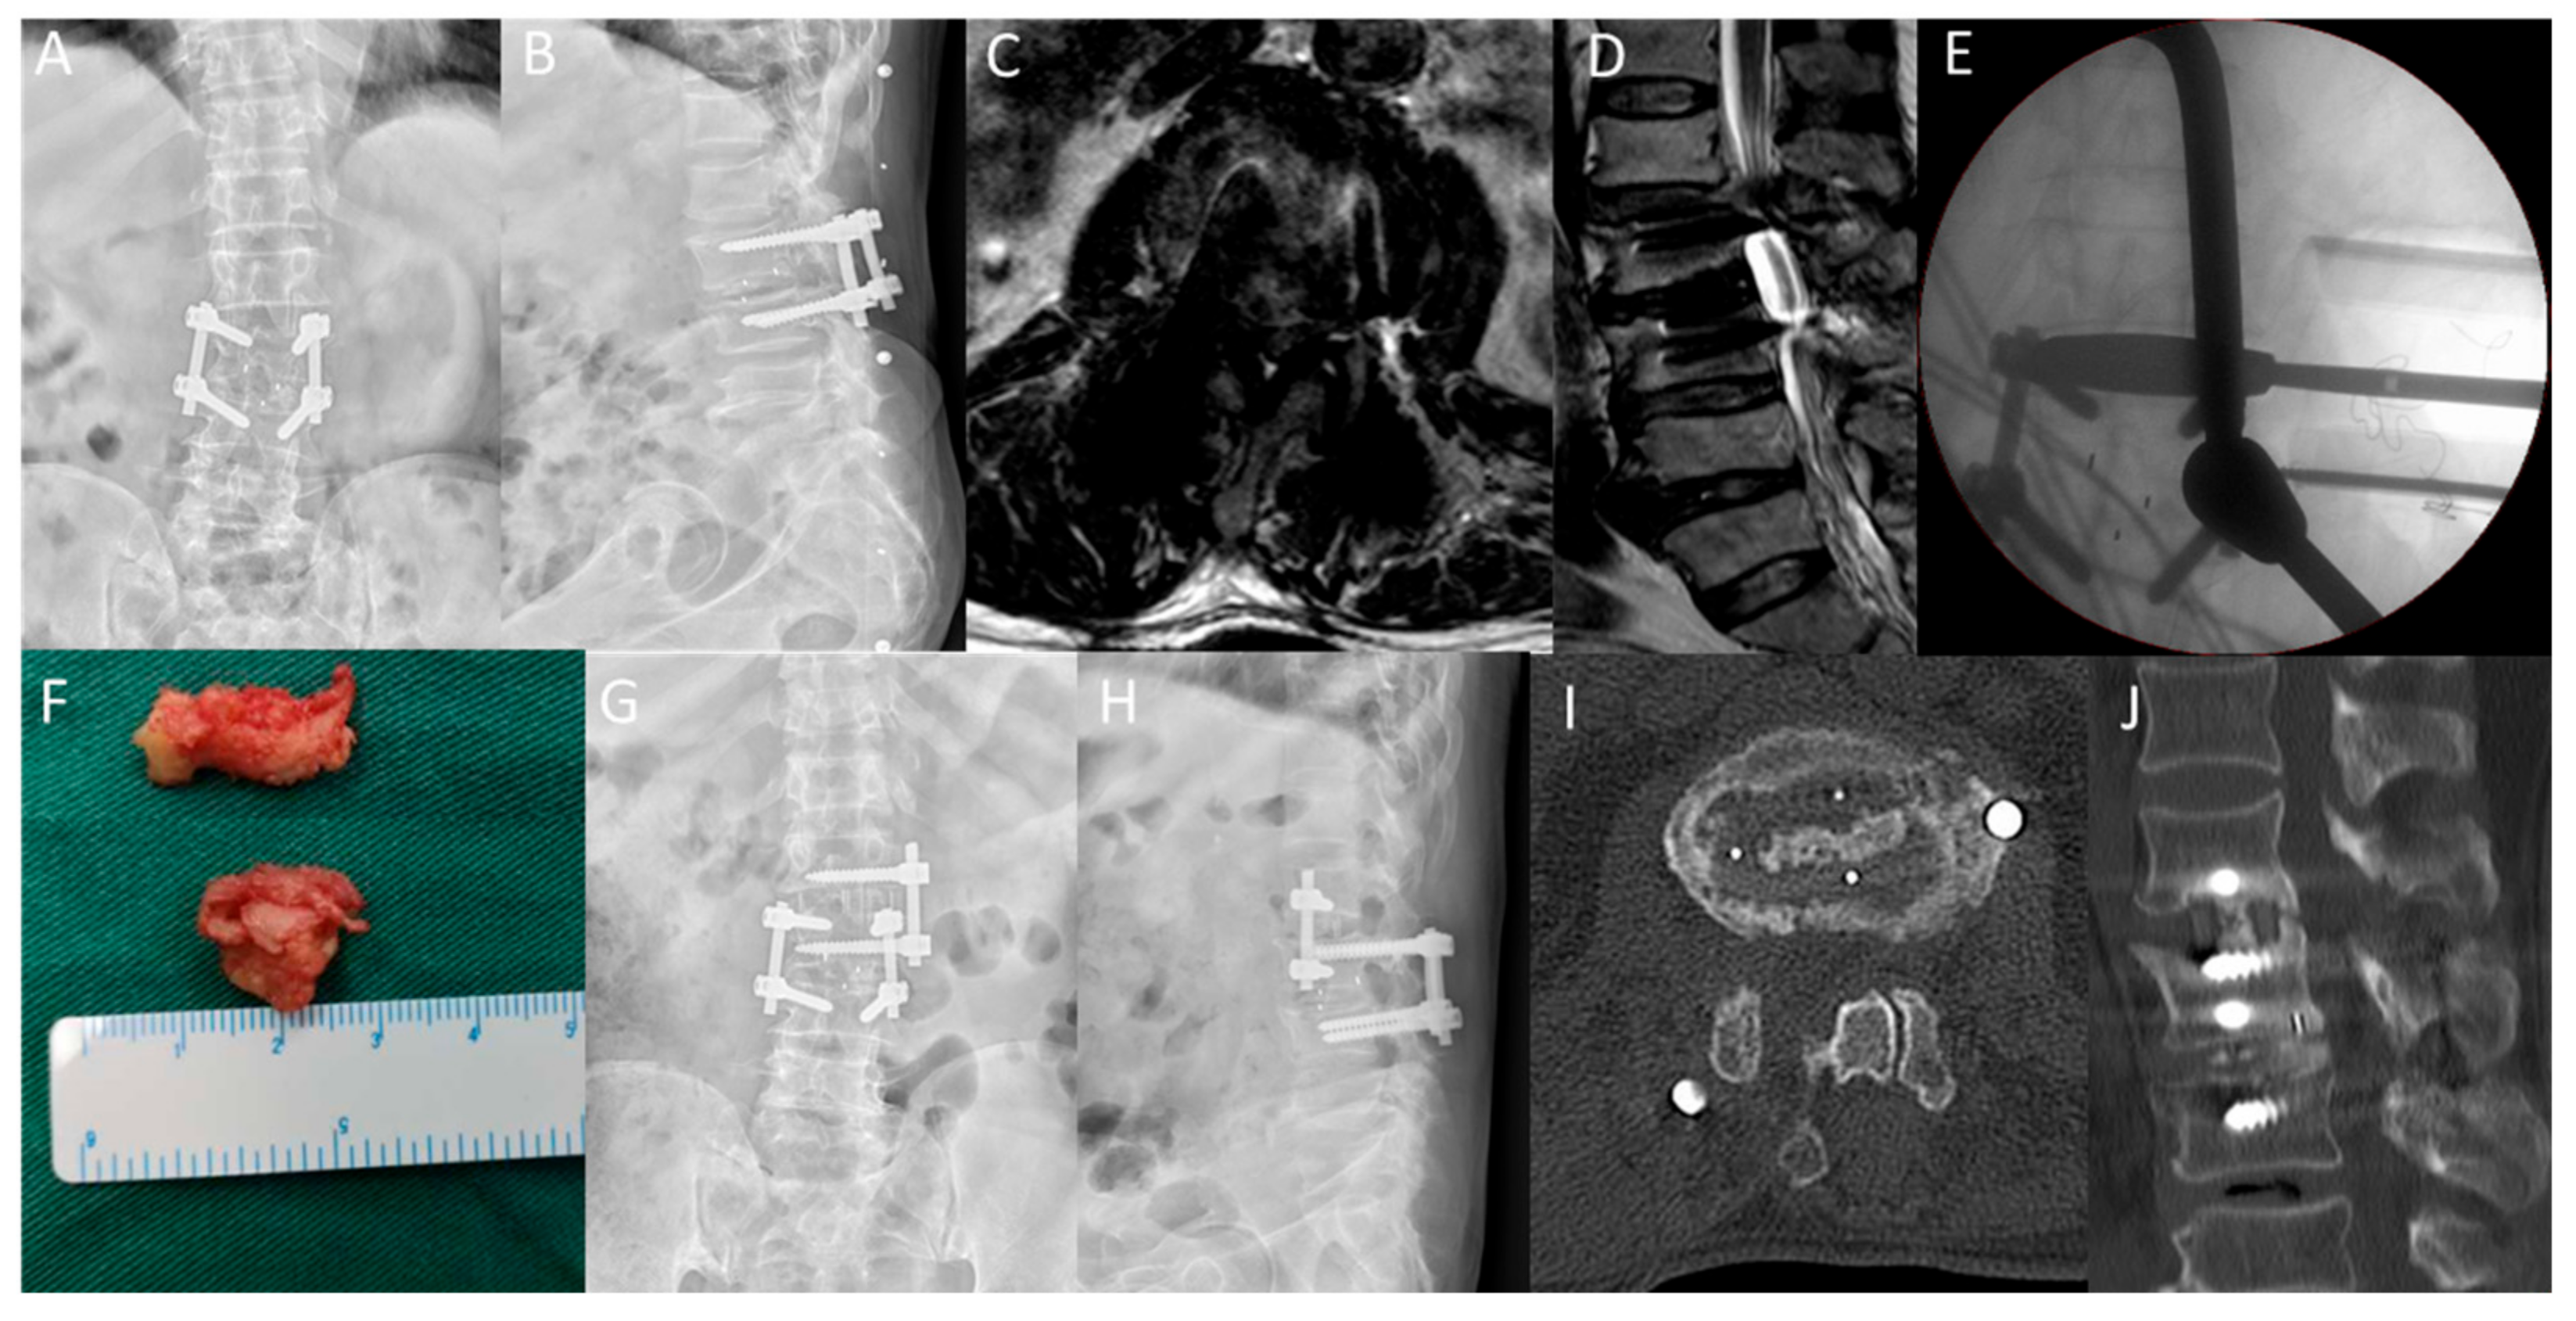

In the OLIF-PD group, the low back pain VAS score was 6.25 ± 1.17 before operation, 2.63 ± 0.74 at two days after operation and 0.63 ± 0.52 at the last follow-up. The VAS score of low back pain in the PLIF group was 6.50 ± 1.32 points before operation, 4.40 ± 0.82 points two days after operation and 1.20 ± 0.62 points at the last follow-up. There was no statistical difference in the preoperative low back pain between the two groups, but the low back pain in the OLIF + PD group was significantly lower than that in the PLIF group at each follow-up time point after surgery, with statistical significance. There was no significant difference in the leg pain scores between the two groups after surgery, three months after surgery and at the last follow-up. The ODI score of the OLIF-PD group decreased from 63.75 ± 8.51 points before operation to 29.25 ± 8.07 points at the last follow-up, and the ODI score of the PLIF group decreased from 64.20 ± 7.02 points before operation to 27.00 ± 4.42 points at the last follow-up. There was no statistical difference between the two groups (Table 3). The excellent and good rate of the modified MacNab standard at the last follow-up was 87.5% (7/8) in the OLIF-PD group and 70% (7/10) in the PLIF group. A typical case is shown in Figure 2.

Figure 2.

The patient, Male, 70 years old, was diagnosed L1/2 adjacent segment disease. (A,B): Anteroposterior and lateral lumbar X-rays suggest lumbar 2/3 internal fixation. (C,D): lumbar MRI revealed lumbar 1/2 disc herniation, significant compression of the dural sac and spinal canal stenosis. (E): C-arm shows the location of the fusion device during OLIF-PD surgery. (F): indicates disc tissue removed during posterior decompression surgery. (G,H): Postoperative lumbar anteroposterior and lateral X indicate good internal fixation position. (I,J): The 1-year follow-up indicated lumbar 1/2 interbody fusion, and the white arrow indicated the posterior bony excision area after channel decompression.